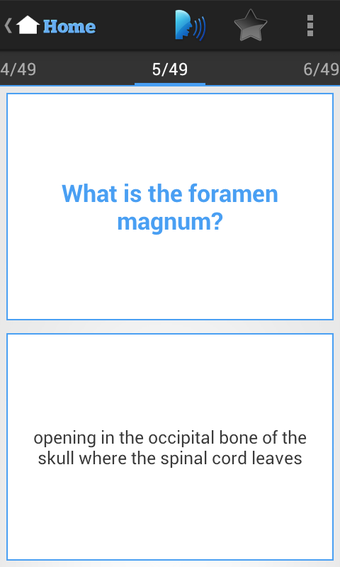

นอกจากนี้ แอปพลิเคชันยังมีการ์ดฝึกหัดเพื่อช่วยให้นักเรียนปรับปรุงคำศัพท์และความรู้ในเชิงการแพทย์ แอปพลิเคชันนี้ใช้ง่ายและวัสดุการเรียนรู้จัดเรียงอย่างดี ทำให้นักเรียนสามารถนำไปใช้ได้อย่างง่ายดาย โดยรวมแล้ว แอปพลิเคชัน USMLE Exam Prep เป็นแหล่งข้อมูลที่ยอดเยี่ยมสำหรับนักเรียนที่กำลังเตรียมตัวสอบ USMLE และเป็นแนะนำอย่างมากสำหรับผู้ที่ต้องการเตรียมตัวสอบอย่างละเอียดและแบบปฏิสัมพันธ์